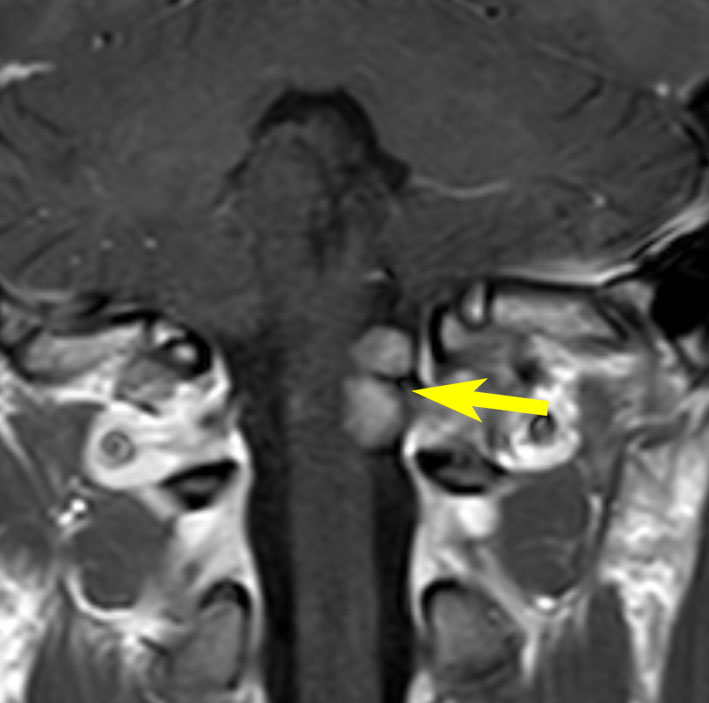

40歳の時に右頸部が腫れているのに気づいて発見され,耳鼻科で生検術され経過をみたものです。7年間の経過観察でかなり増大しました。症状は全くありませんでした。まだ腫瘍増大が止まらないので摘出することにしました。術前は舌咽神経鞘腫と診断することはできません。

手術中に中枢端で舌咽神経本幹に連続性がありここを切断して全摘出しました。それで舌咽神経鞘腫と確定診断ができています。

術後には無症状,他覚的な神経脱落症状はありませんでした。長い間かかって増大したので迷走神経などで代償機能が働いているのだと推定されます。

舌咽神経の末梢枝は,carotid sinusからの感覚神経を含むので,内頸動脈と外頸動脈の間に入り込むように増大することがあります。